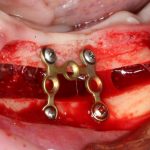

Изоляция области аутографта и имплантатов барьерной мембраной.

Перекрывать костный блок барьерной мембраной или оставить так? По этому вопросу есть много мнений. Между тем, в публикации по методике есть ясное показание, когда это требуется.

Конкретно в этом клиническом случае между костным аутотрансплантатом, ложем и имплантатами есть пустое пространство. Если его не изолировать от мягких тканей, они прорастут и осложнят интеграцию аутографта. Поэтому я решил перекрыть костный блок барьерной мембраной, пусть это делает хирургическую операцию немного дороже.

— я использовал барьерную мембрану Geistlich Bio-Gide, которая имеет две разные поверхности: с одной стороны она рыхлая «адгезивная», с другой — гладкая и прочная. Как укладывать — на результат не влияет, но в плане удобства рыхлую поверхность мы «приклеиваем» к тому, на чем требуется барьерную мембрану удержать. В данном случае хотелось бы удержать её на костной поверхности — следовательно, мы укладываем её рыхлой поверхностью к кости.

— ты знаешь, что барьерная мембрана может выполнять две функции, каркасную и изолирующую. Первая функция требует обязательной фиксации и натяжения, вторая — нет. В нашем случае «каркасом» регенерата является костный блок, а барьерная мембрана нужна только для изоляции. Поэтому она не требует натяжения и фиксации пинами.

После я внимательно проверил, что костный блок и имплантаты полностью перекрыты. Теперь рану можно ушивать.